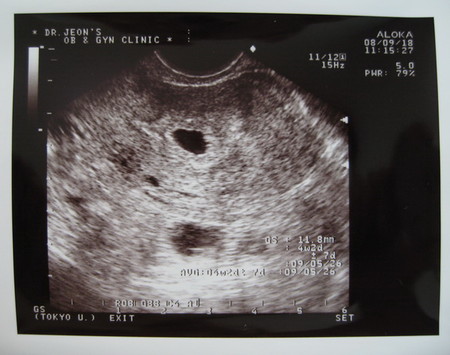

Первое УЗИ

А сегодня я была у врача, сделали УЗИ. У нас все отлично, прикрепился где надо, не высоко и не низко. Растет соот-но сроку. Сейчас уже 11.8 мм. Я правда ожидала что сердечко смогу послушать, но врач сказала что еще рано.

Вот полюбуйтесь на мое УЗИ: